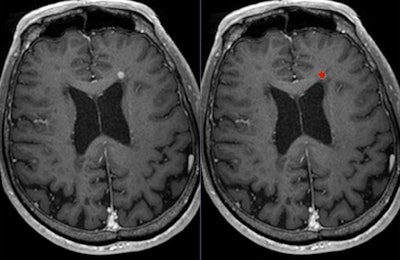

High-resolution T2-weighted (above) and enhanced T1-weighted (below) images of large intra- and extrameatal vestibular schwannoma. All images courtesy of Dr. Francesca Pizzini."Gadolinium-based contrast agents increase the relaxation rate of water protons in the region where they distribute, thus providing relevant information on pathologies, involving changes in the vascular density and permeability and structural differences," she said. "Unenhanced sequences available are not currently providing comparable and alternative structural details."